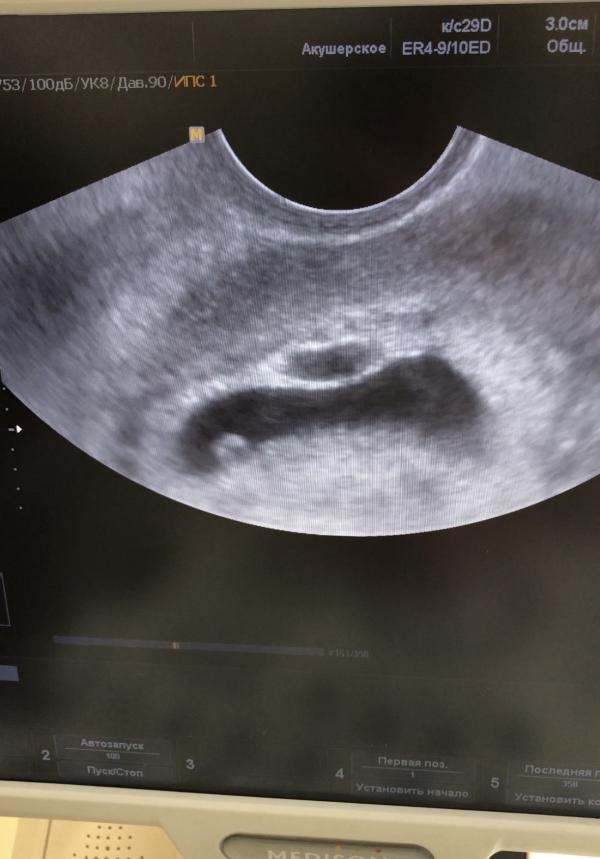

🤰🏼В прошлом посте я рассказала, как мы узнали о беременности. На сроке 7.5 недель я пошла на 2 узи, где уже должно было прослушиваться сердцебиение эмбриона. Но врач сказал, что беременность не развивается. В нем есть желточный мешок, а эмбрион так и не появился.

При здоровой беременности на таком сроке это невозможно. Кроме того, на узи он увидел второе плодное яйцо, которое было не видно на сроке 5 недель (такое часто бывает с двойнями). И там тоже не было эмбриона.